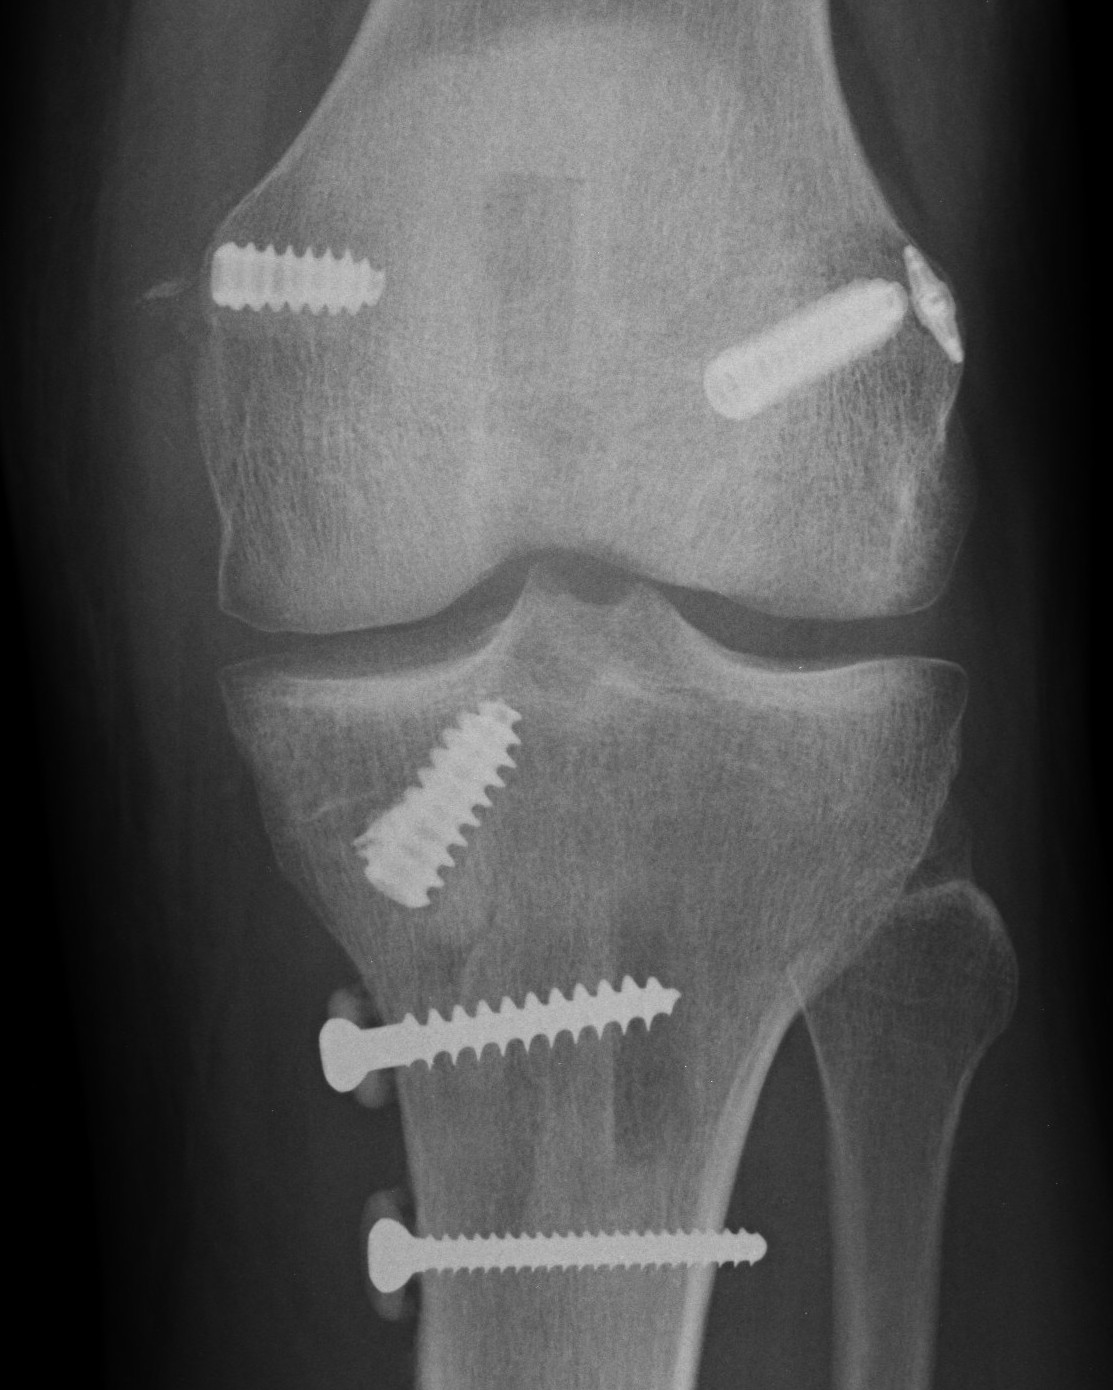

Bony MCL Avulsion

Elevate VMO and repair with staples or screw

Advancement of proximal MCL / POL with screw, and imbrication / tightening of POL

Advancement of femoral MCL and staple / suture anchor fixation

3. Reconstruction of MCL and posteromedial corner

A. Single bundle anatomic allograft MCL reconstruction (no POL)

Femoral attachment

- 4 mm proximal and posterior to medial epicondyle

- image intensifier: intersection of the posterior femoral condyle with Blumensaat's line

- 40o anterior to avoid notch

- 40o proximal to avoid PCL tunnel

Tibial attachment

- 6 cm from joint line

- just posterior to pes attachment